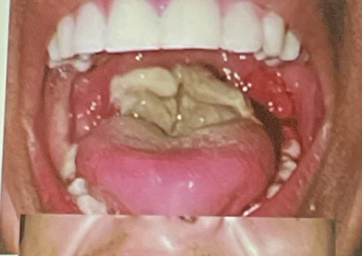

como es la fase aguda de la difteria respiratoria?

A

• faringitis pseudomembranosa

• invade laringe

• sangrado al desprenderse

• ES LA + PELIGROSA